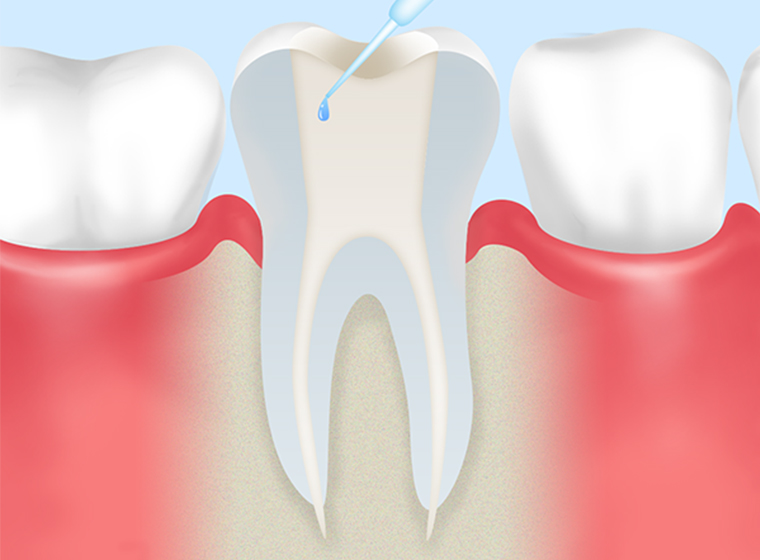

- STEP3

根管内の消毒・除菌 -